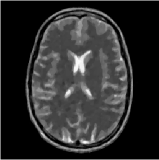

V-D Reconstruction Performance

To evaluate the improvements of accuracy in our method in the actual reconstruction problems, we perform experiments where the measurement was generated by the reference projector and reconstructed with different approximating projectors (i.e., SF, LTRI and CNSF). The optimizer used in the experiments is adaptive steepest descent POCS regularized by total-variation (TV) called ASD-POCS [5] and all the hyper-parameters are adjusted to achieve the highest reconstruction quality for each model.

In this experiment, we use Shepp-Logan and the Brain phantom with resolution (128 mm×128 mm128 mm128 mm128\text{ mm}\times 128\text{ mm}) and (256 mm×256 mm256 mm256 mm256\text{ mm}\times 256\text{ mm}) respectively as the benchmark dataset. The simulated flat detector X-ray system is configured with Ns=409subscript𝑁𝑠409N_{s}=409, Dpo=200subscript𝐷𝑝𝑜200D_{po}=200 mm, Dso=200subscript𝐷𝑠𝑜200D_{so}=200 mm and Ns=815subscript𝑁𝑠815N_{s}=815, Dpo=400subscript𝐷𝑝𝑜400D_{po}=400 mm, Dso=400subscript𝐷𝑠𝑜400D_{so}=400 mm. The detectors are spaced by Δs=1subscriptΔ𝑠1\Delta_{s}=1 mm with bin width τ=1𝜏1\tau=1 mm and the projectors are uniformly spaced over 360superscript360360^{\circ}. Fig. 12 shows the reconstruction result of Shepp-Logan phantom. The (imperfect) reconstruction achieved by reference projector in Fig. 12(a) illustrates the practical reconstruction problem from limited-view projection. The approximating projector made by LTRI results in a less accurate reconstruction (the resolution of look-up table in LTRI is 10000×1801000018010000\times 180). SF makes a slightly more accurate approximation and achieves a little higher quality over LTRI. Our method provides a reconstruction that can achieve the same quality as the one provided by reference projector.

Figure 12: Reconstruction of Shepp-Logan phantom from 161616 uniformly spaced projections using ASD-POCS.

Fig. 13 shows the reconstruction of the brain phantom. In order to evaluate the impact of the accuracy of the forward model in image reconstruction, we visualize the differences of all reconstructions from the reconstruction provided by reference model that is shown in 13(a). For visualization purpose, we scale the errors by appropriate factors shown in captions. The SNRs for these results are (Ref) 19.3819.3819.38dB, (LTRI) 18.9618.9618.96dB, (SF) 19.0719.0719.07dB, (CNSF) 19.3819.3819.38dB respectively.

This experiment shows significant improvements over LTRI and SF methods in image reconstruction.